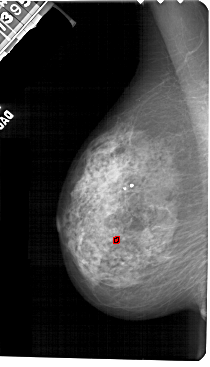

A_1544_1.LEFT_MLO

LEFT_MLO LINES 5491 PIXELS_PER_LINE 3136 BITS_PER_PIXEL 12 RESOLUTION 43.5 OVERLAY

FILE: A_1544_1.LEFT_MLO.OVERLAY

TOTAL_ABNORMALITIES 1

ABNORMALITY 1

LESION_TYPE CALCIFICATION TYPE VASCULAR DISTRIBUTION LINEAR

ASSESSMENT 2

SUBTLETY 2

PATHOLOGY BENIGN

TOTAL_OUTLINES 1

BOUNDARY